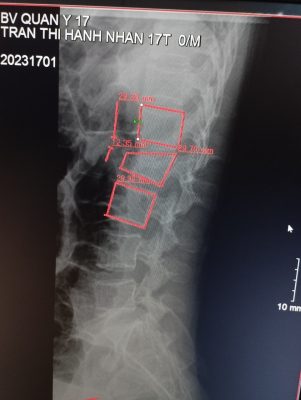

– Kết quả chụp phim chẩn đoán: chấn thương mất vững cột sống vỡ lún L2, có tổn thương thành sau thân đốt sống.

Phim Xquang cột sống